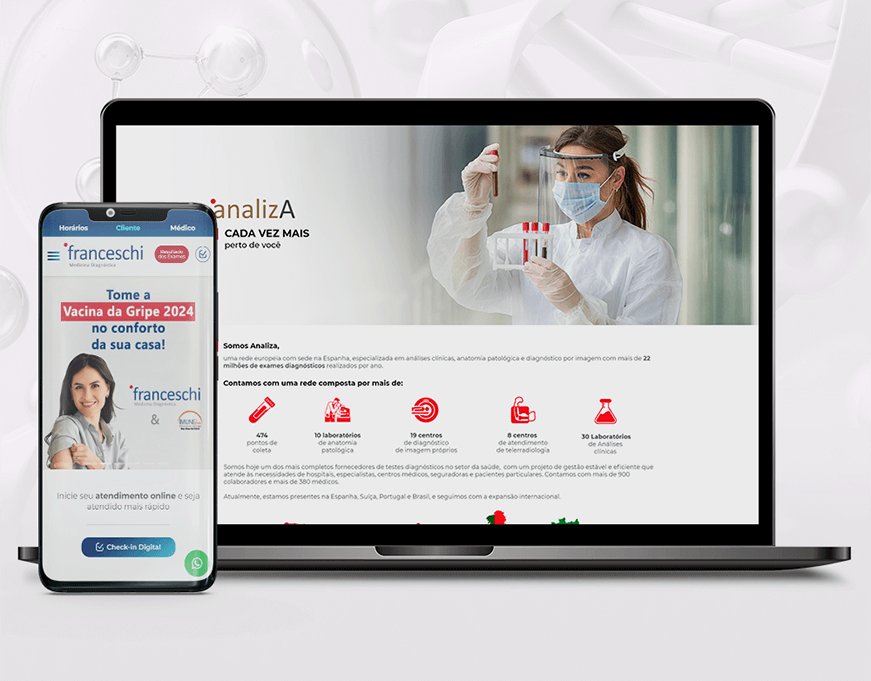

Tecnologia

Soluções na nuvem, atuamos na criação de softwares e sistemas web personalizados.

Sites corporativos

Sistemas Web

UX/UI

Front-end

Back-end

Banco de dados

E-commerce

Landing Pages

WordPress

Website Hosting